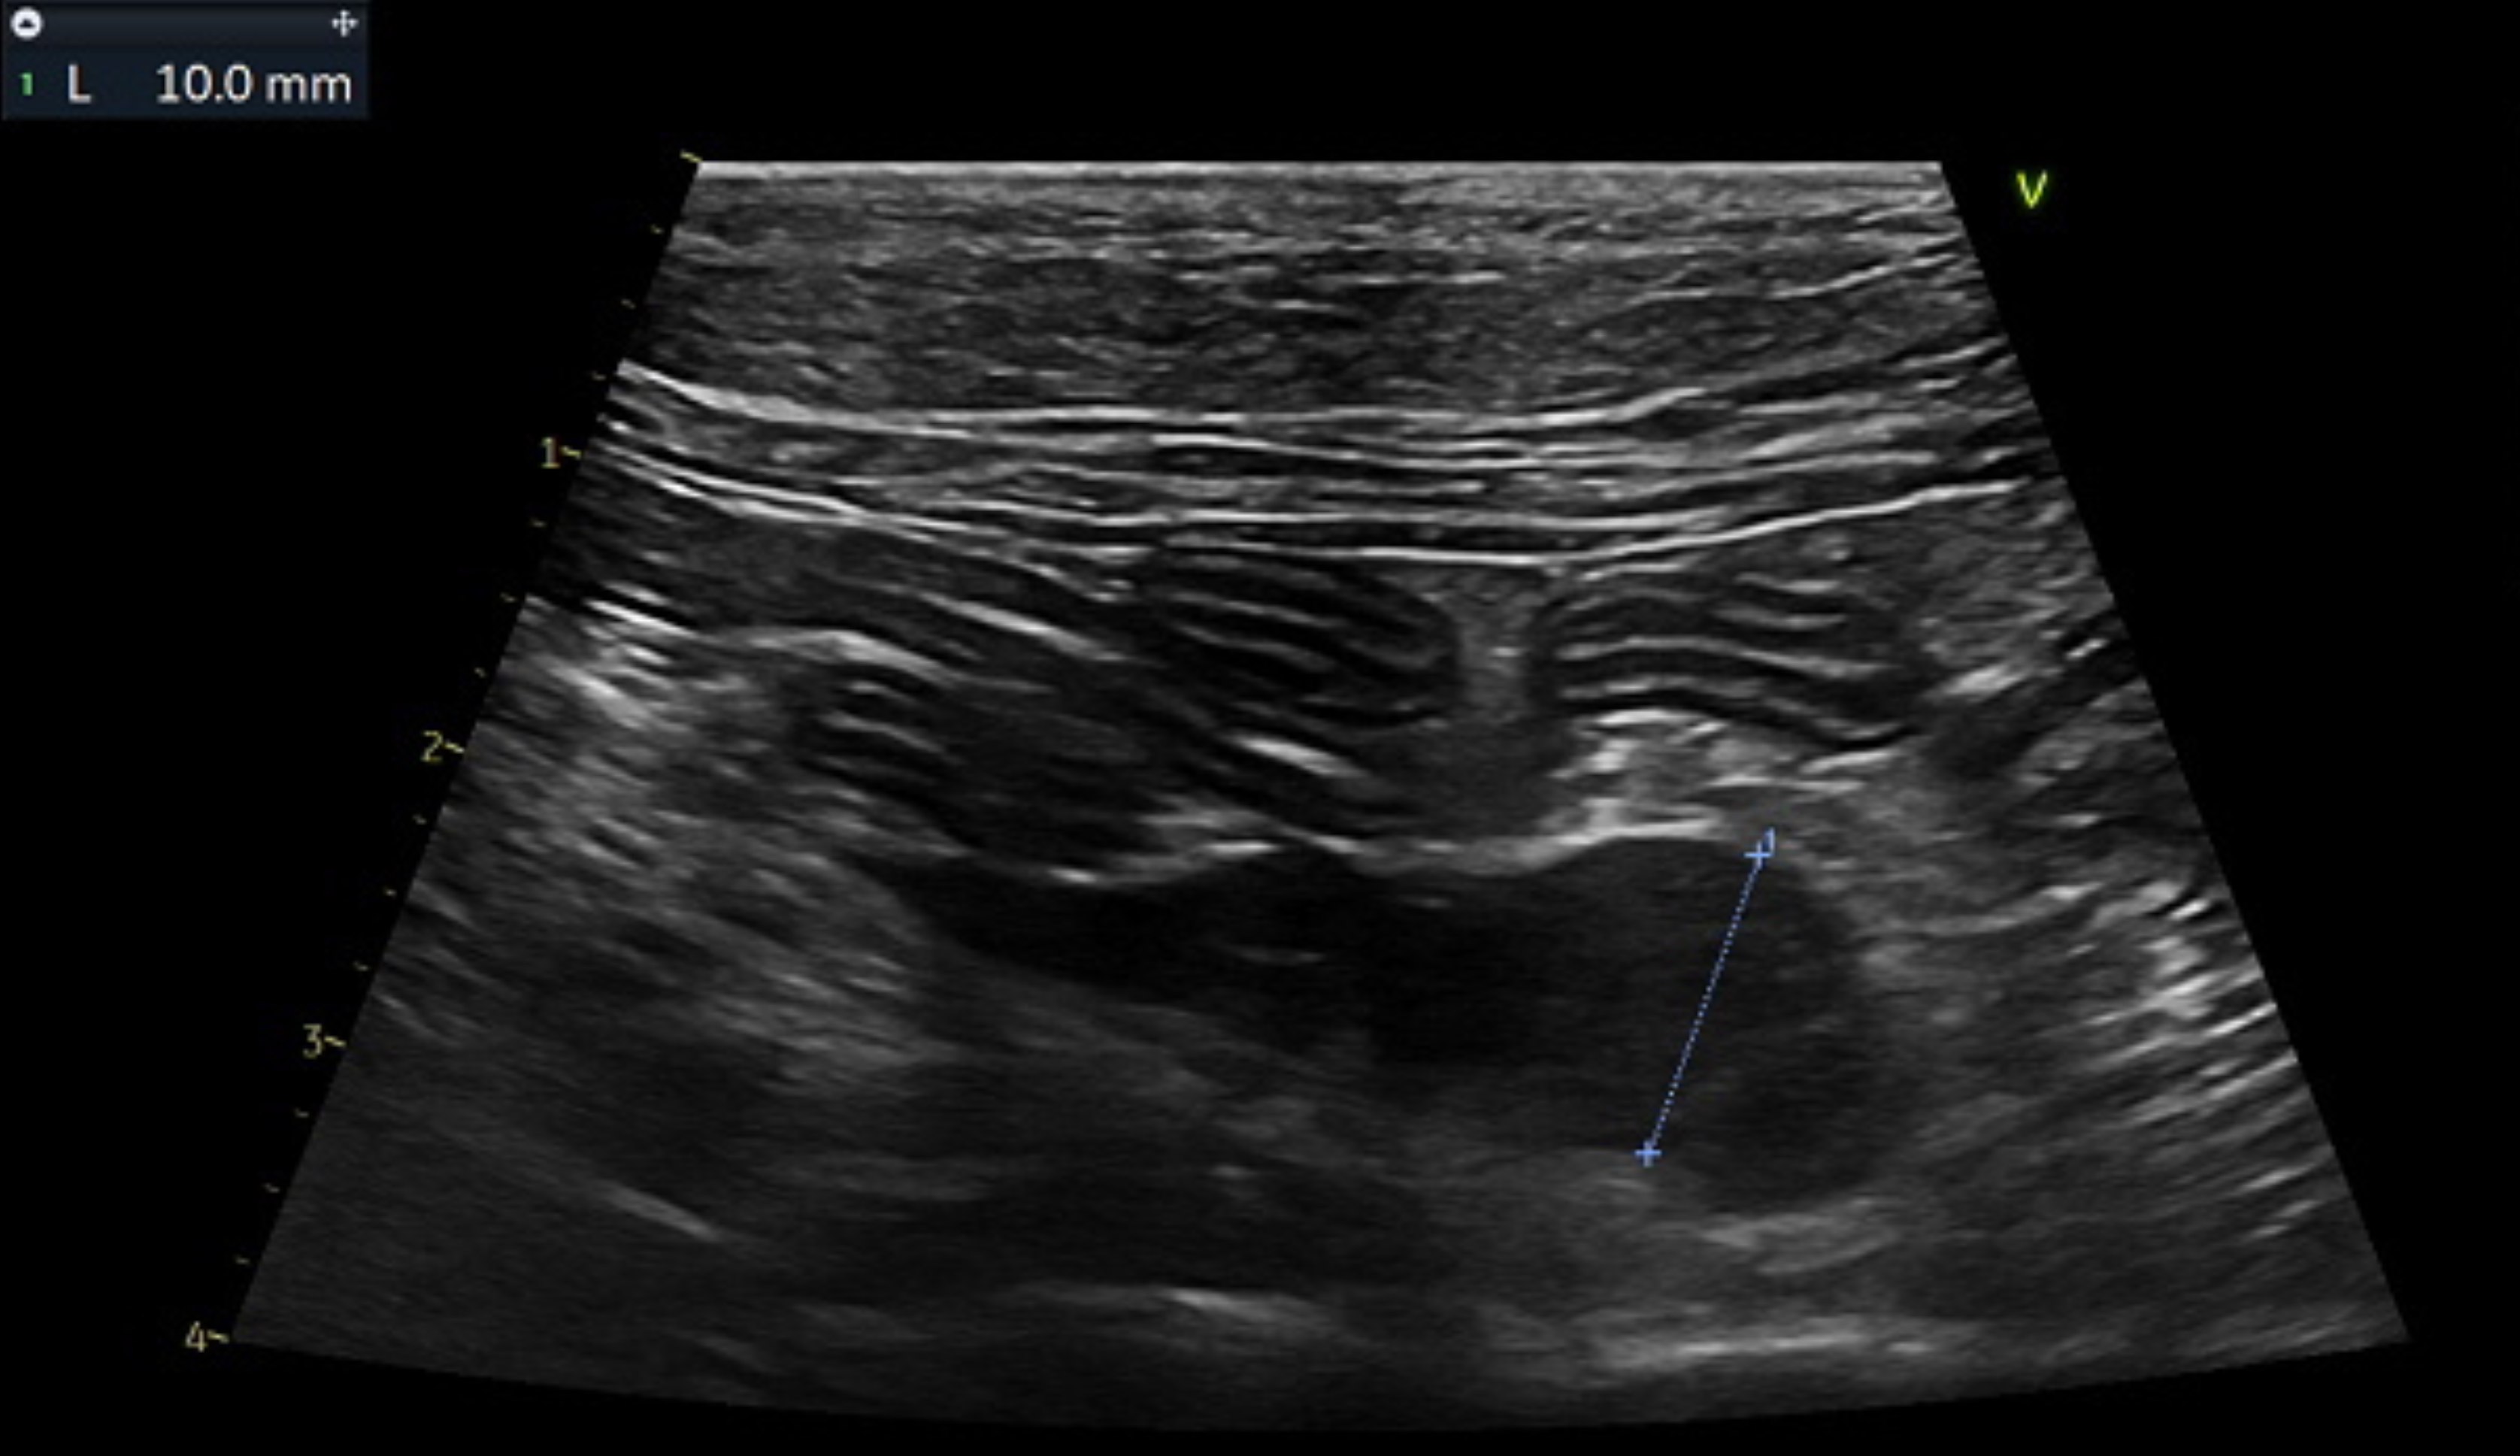

腹部超音波検査において腹腔内の腸管付近のリンパ節が1.0cm程度(正常は<0.5cm)と軽度腫大をしていたため、2週間後に再度超音波検査にて再確認しましたがサイズに変化はありませんでした。超音波検査において消化管を含めて他臓器に明らかな異常は認めませんでしたが、腫大しているリンパ節の細胞診およびCT画像検査と消化管の内視鏡生検検査をご提案し、念のため実施することとなりました。

※写真は腹部超音波にて空腸リンパ節のサイズを測定しているところです